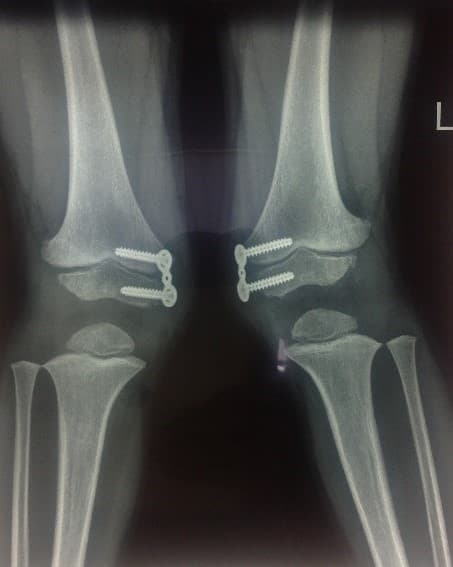

Пример применения гемиэпифизиодеза №2:

Идиопатичпеская вальгусная деформация бедер

Через 8 месяцев­­­